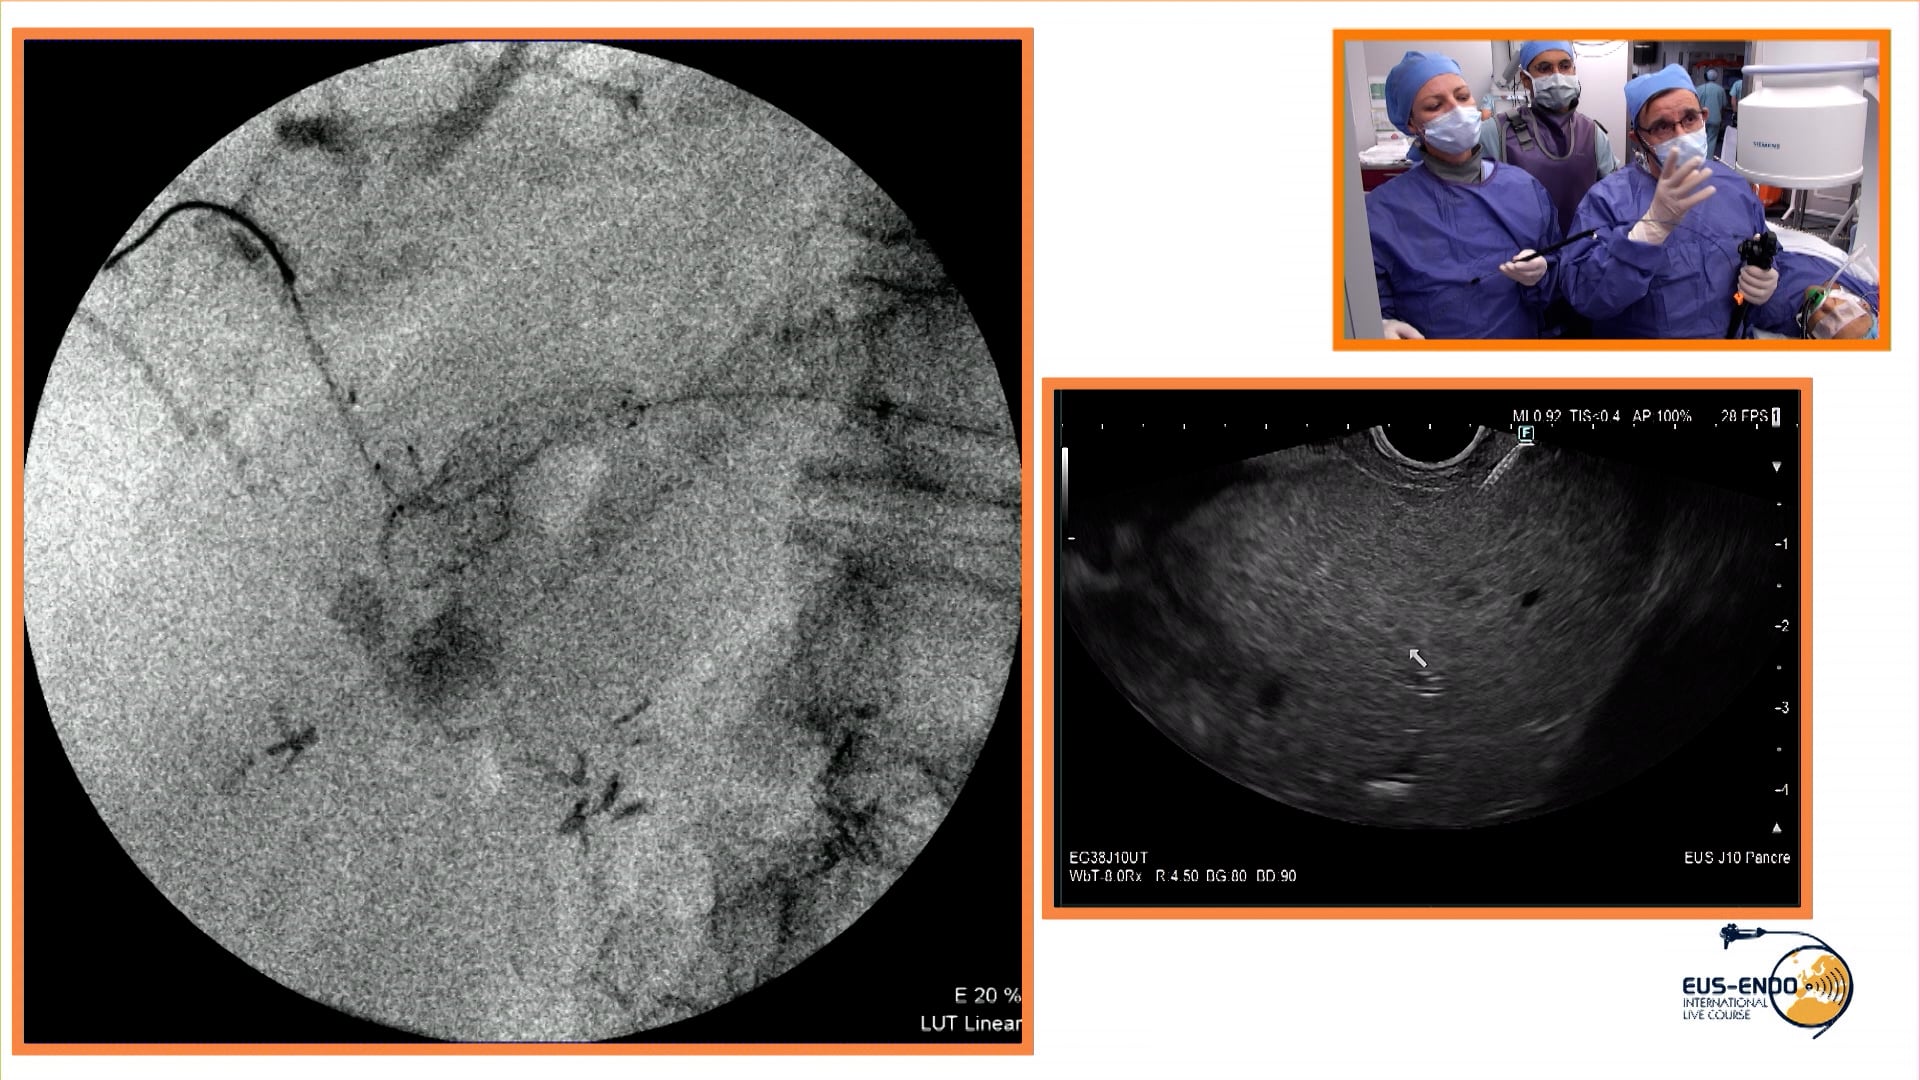

Endoscopic ultrasound-guided biliary drainage using the bridging technique for hepatic hilar metastasis from a pancreatic neuroendocrine tumor (pNET) causing jaundice